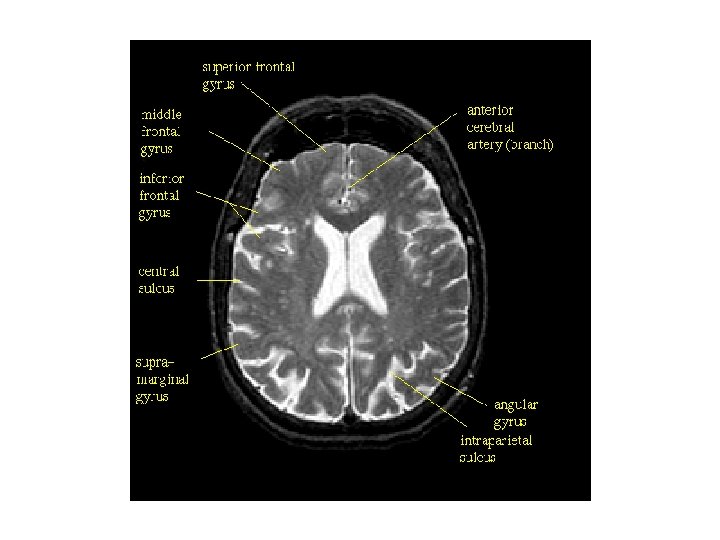

대뇌 외측표면에서 관찰되는 구조 1. 외측고랑(lateral fissure) 3. 하전두이랑 안와부(pars orbitalis) 5. 하전두이랑 삼각부(pars triangularis) 7. 하전두이랑 판개부(pars opercularis) 9. 상전두이랑(superior frontal gyrus, 상전두회) 11. 상전두고랑(superior frontal sulcus, 상전두구) 13. 중심전이랑(precentral gyrus, 전중심회) 15. 중심후이랑(postcentral gyrus, 후중심회) 17. 두정엽내고랑(intraparietal sulcus) 19. 변연상이랑(supramarginal gyrus, 연상회) 21. 두정후두고랑(parieto-occipital sulcus) 23. 외측후두이랑(lateral occipital gyrus) 25. 외측고랑 뒷가지(posterior ramus, 후지) 27. 하측두이랑(inferior temporal gyrus) 29. 상측두고랑(superior temporal sulcus) 31. 측두극(temporal pole) 2. 전두극(frontal pole) 4. 외측고랑 앞가지(anterior ramus, 전지) 6. 외측고랑 오름가지(ascending ramus, 상행지) 8. 하전두고랑(inferior frontal gyrus, 하전두구) 10. 중간전두이랑(middle frontal gyrus, 중전두회) 12. 중심전고랑(precentral sulcus, 전중심구) 14. 중심고랑(central sulcus, 중심구) 16. 중심후고랑(postcentral sulcus, 중심후구) 18. 상두정소엽(superior parietal lobule) 20. 각이랑(angular gyrus, 각회) 22. 후두극(occipital pole) 24. 후두전패임(preoccipital notch) 26. 하측두고랑(inferior temporal sulcus) 28. 중간측두이랑(middle temporal gyrus) 30. 상측두이랑(superior temporal gyrus)